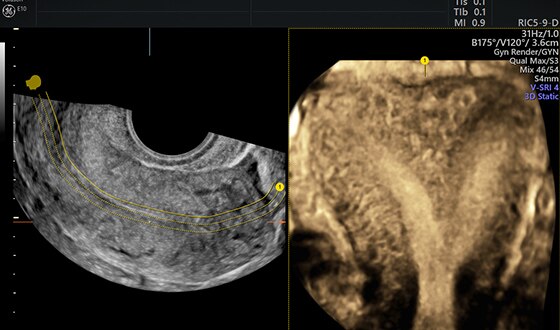

Tomographic ultrasound imaging (TUI) of uterine cavity